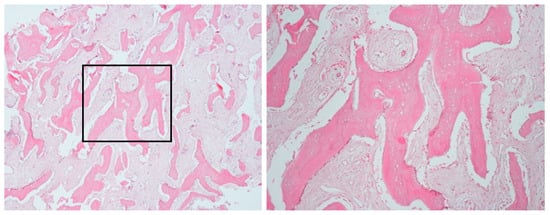

2.1.3. Histopathological Examination

2.2.3. Histopathological Examination

| 1 | 11 | Left mandible (#32–#37) | Mixed sclerotic and lytic lesion with buccolingual expansion and “onion-skin” periosteal reaction | Irregular bone and fibrous tissue, sclerosis, no inflammation or bacteria | Long-term antibiotic course, NSAIDs | CNO confirmed by imaging, histology, and initial failure to respond to antibiotics | Conservative; antibiotics discontinued after improvement | Improved at 7 months; recurrence at 18 months; no further treatment needed |

| 2 | 9 | Right mandible (#33–#47, crossing midline) | Patchy sclerotic and radiolucent lesion, mandibular expansion, double cortex | Viable bone with osteoblastic rimming, no bacterial colonies | Multiple antibiotics, extractions, NSAIDs | CNO based on imaging, histology, and clinical course | NSAIDs only; progressive improvement | Gradual resolution with NSAIDs |